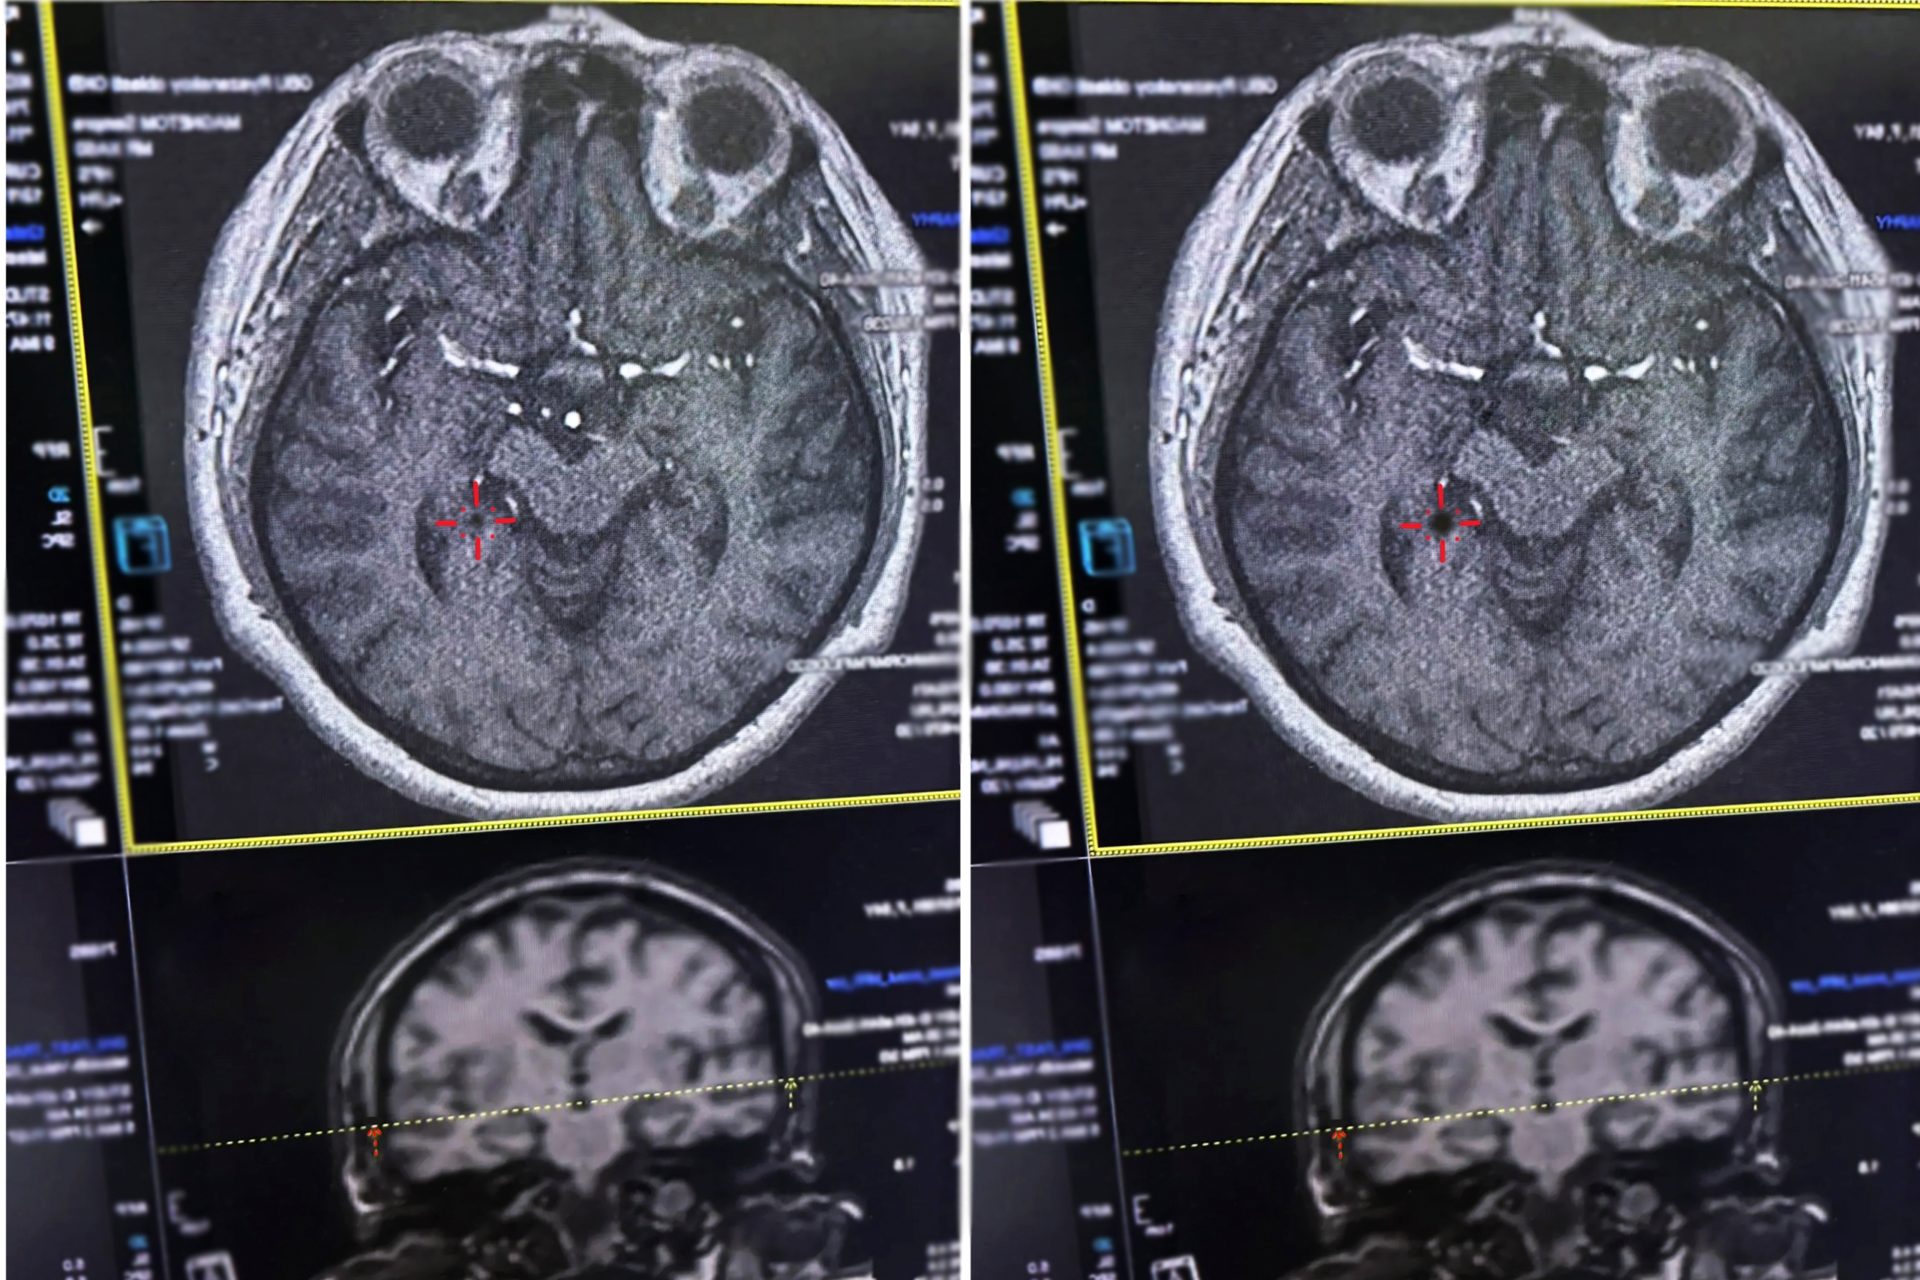

Как поясняют врачи, при ишемическом инсульте кровоток по сосуду, питающему мозг, прекращается. Лишённый кислорода участок нервной ткани начинает быстро погибать. В этот момент крайне важно успеть восстановить кровоснабжение, растворив тромб специальными препаратами, и сделать это можно только в первые часы.

Помощь, оказанная в этот период, максимально эффективна не только для спасения жизни, но и для восстановления утраченных функций. Именно тогда можно кардинально повлиять на течение инсульта и спасти гибнущие клетки мозга, – отмечают специалисты.